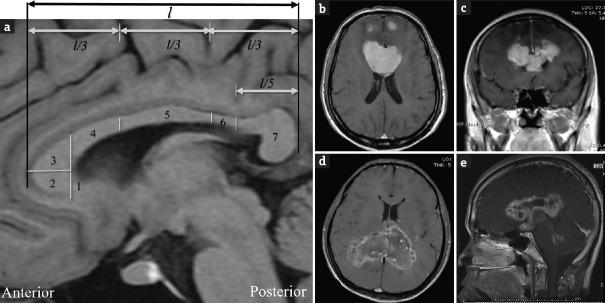

The pathologies implicate the bilateral corpus callosum that builds the butterfly pattern on axial view. These tumors have seldom been investigated for both clinical manifestations and outcome.

这些病变累及双侧胼胝体,在轴位视图上形成蝴蝶样形态。对于这些肿瘤的临床表现和预后,此前鲜有研究。